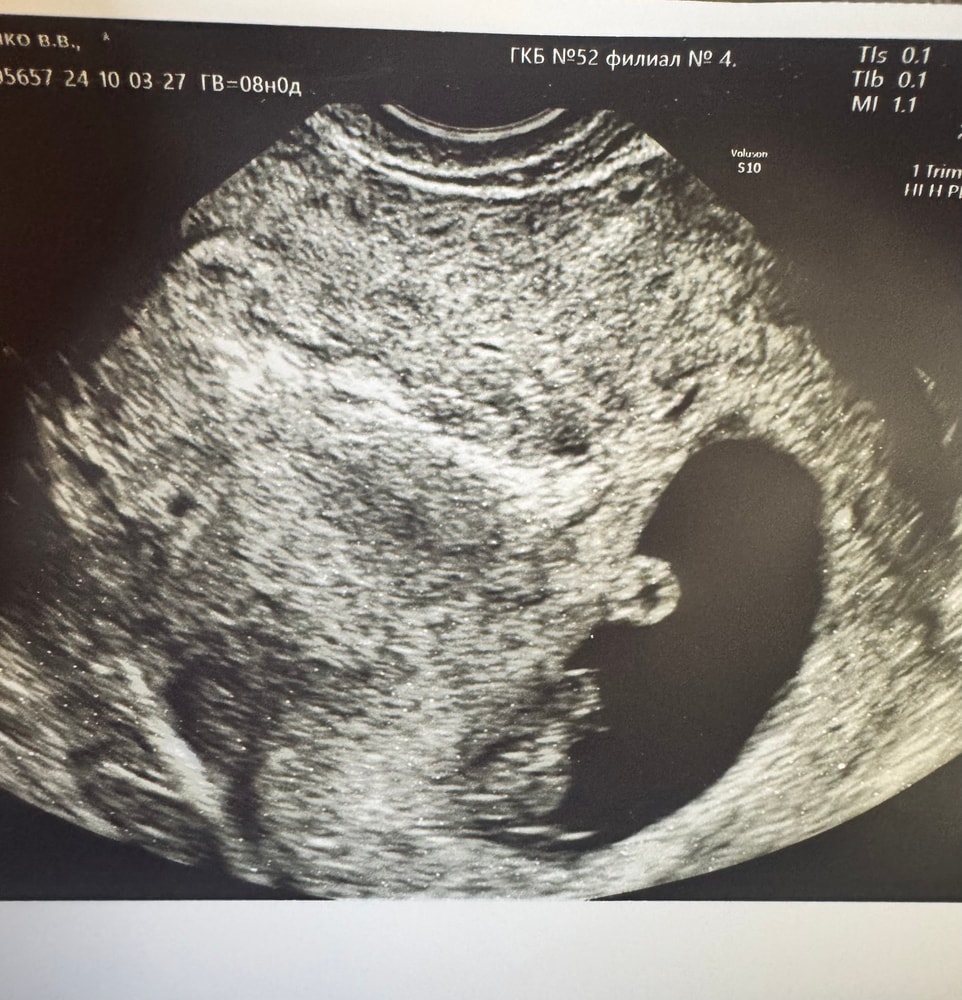

Valeri, у меня вот такое было в 8 Нед Изображение

Мне говорили о тонусе при таком яйце, но в то же время говорили, что для срока норм и оно станет нормальным. Попила магний и всё ок было

Да это так на узи получилось , все нормально у вас